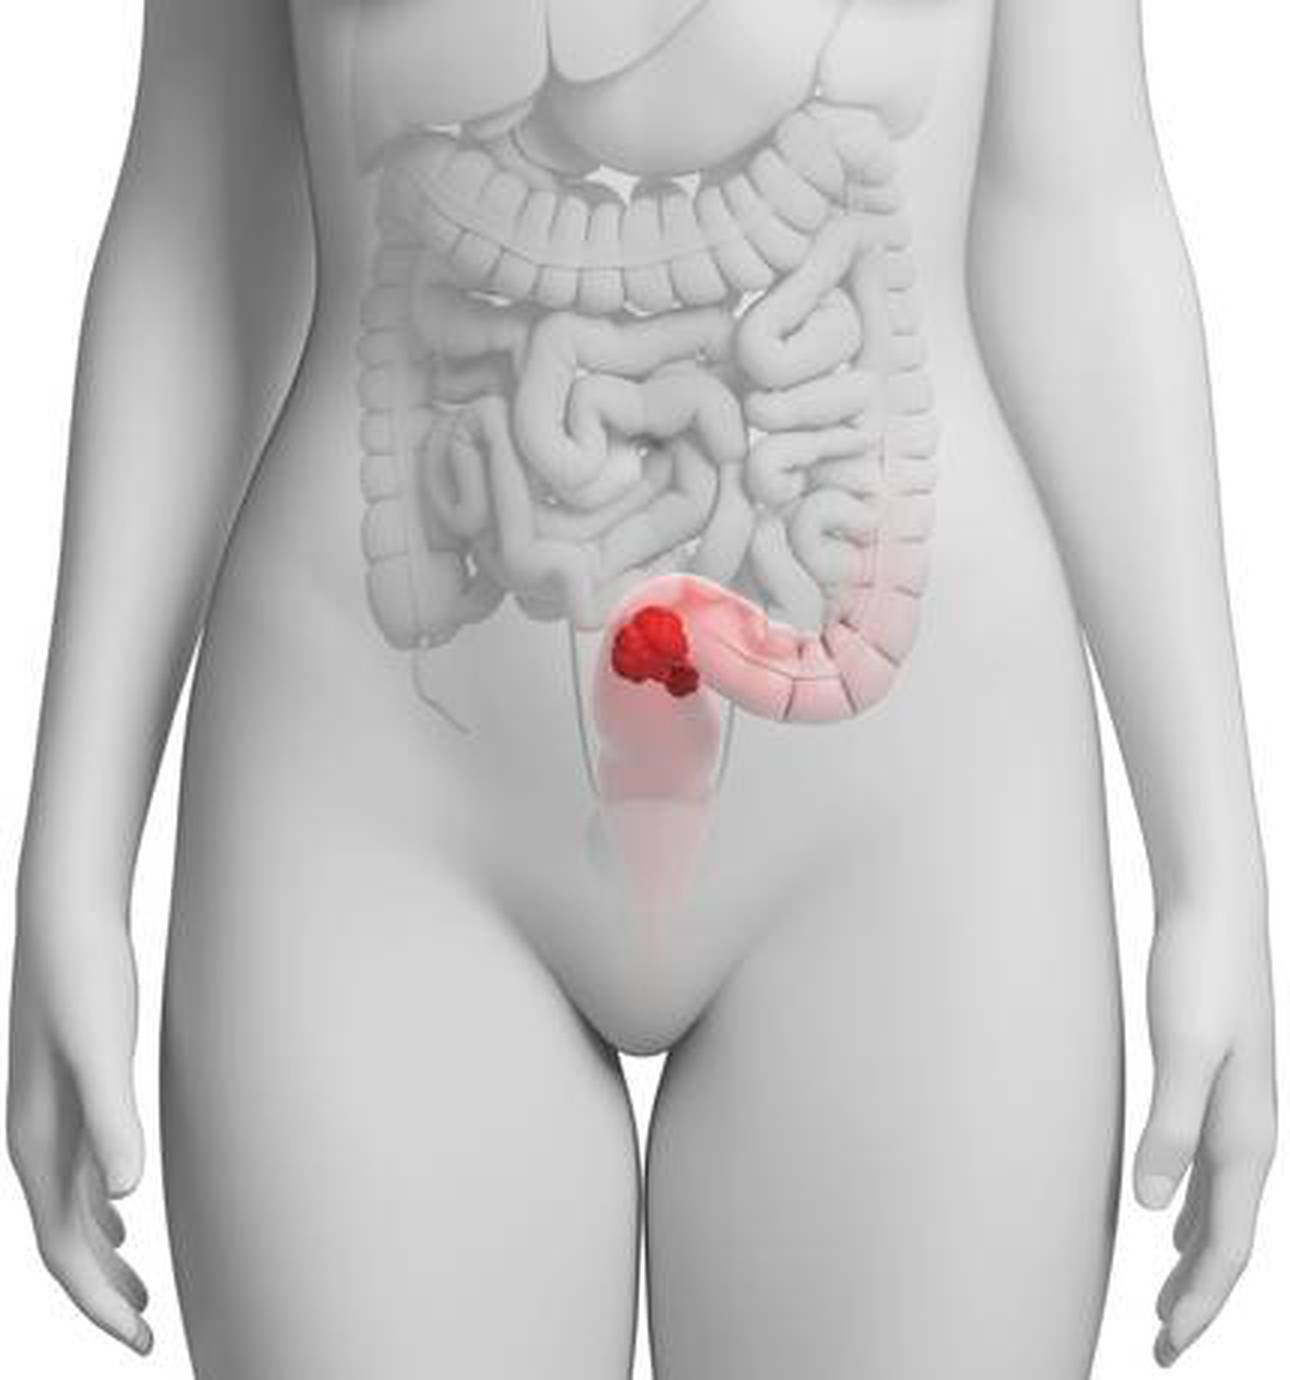

St Mark’s already offers complex treatments for patients with advanced and recurrent bowel cancer and is one of a handful of units across the UK offering complex interventions.

The surgical work at St Mark’s Hospital specialises in advanced techniques for the treatment of both common and unusual problems of the small and large bowel and of the anus.

The inherited intestinal cancer syndromes are more commonly known as polyposis and Lynch Syndrome.